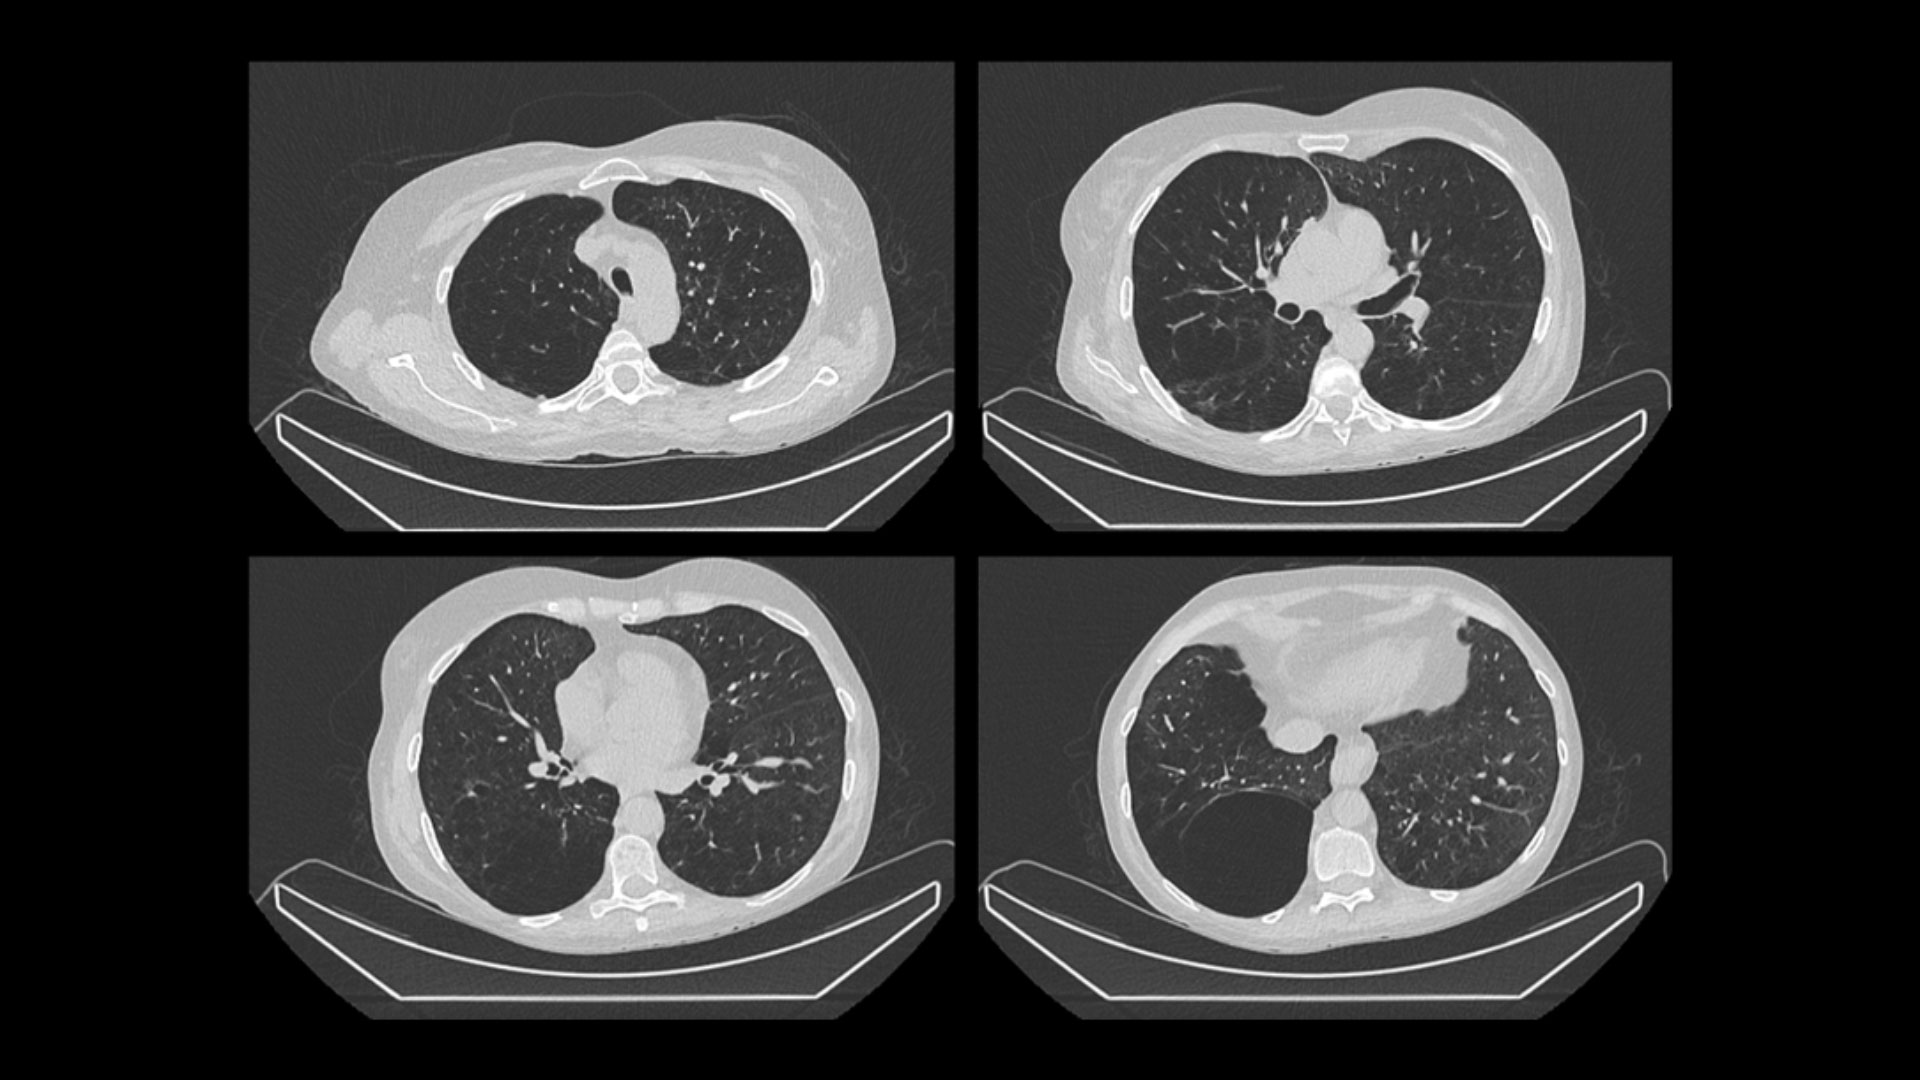

Advanced hybrid CT

SPECT/CT with the specifications of an advanced standalone CT

With its 40 mm detector, Aurora achieves twice the detector coverage compared to CTs of other hybrid systems.¹¹ Aurora's 0.35 second rotation speed¹² and 2X detector coverage open up your clinic to performing advanced cardiac procedures.

Aurora's Revolution Ascend expands your CT versatility

Beyond routine CT exams, such as low-dose lung screenings and calcium scoring, Aurora can perform advanced CT procedures like coronary CT angiography (CCTA) and multi-phase CT.